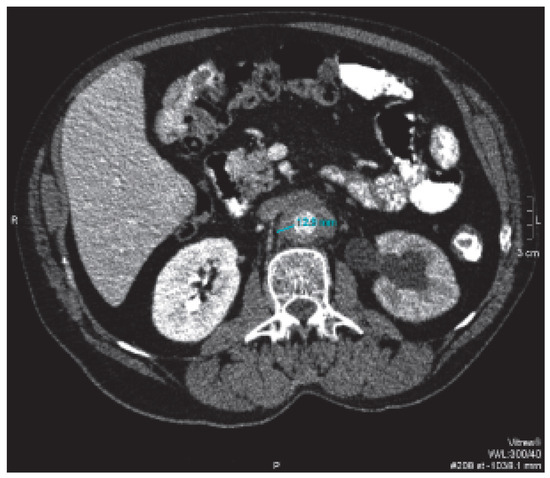

M. Ormond (retroperitoneale Fibrose)

by Y. Suter, A. Cornelius and D. Conen

Ein 49jähriger Patient stellte sich mit seit zwei Monaten anhaltenden rezidivierenden kolikartigen Oberbauchschmerzen vor. Es wurde bei Cholezystolithiasis eine Cholezystektomie durchgeführt. Während der Hospitalisation fiel eine Erhöhung der Transaminasen ohne sonographisches Korrelat auf. Eine postoperative Computertomographie des Abdomens liess ein retroperitoneales Hämatom vermuten [...] Read more.

Ein 49jähriger Patient stellte sich mit seit zwei Monaten anhaltenden rezidivierenden kolikartigen Oberbauchschmerzen vor. Es wurde bei Cholezystolithiasis eine Cholezystektomie durchgeführt. Während der Hospitalisation fiel eine Erhöhung der Transaminasen ohne sonographisches Korrelat auf. Eine postoperative Computertomographie des Abdomens liess ein retroperitoneales Hämatom vermuten (Abb. 1). [...] Full article